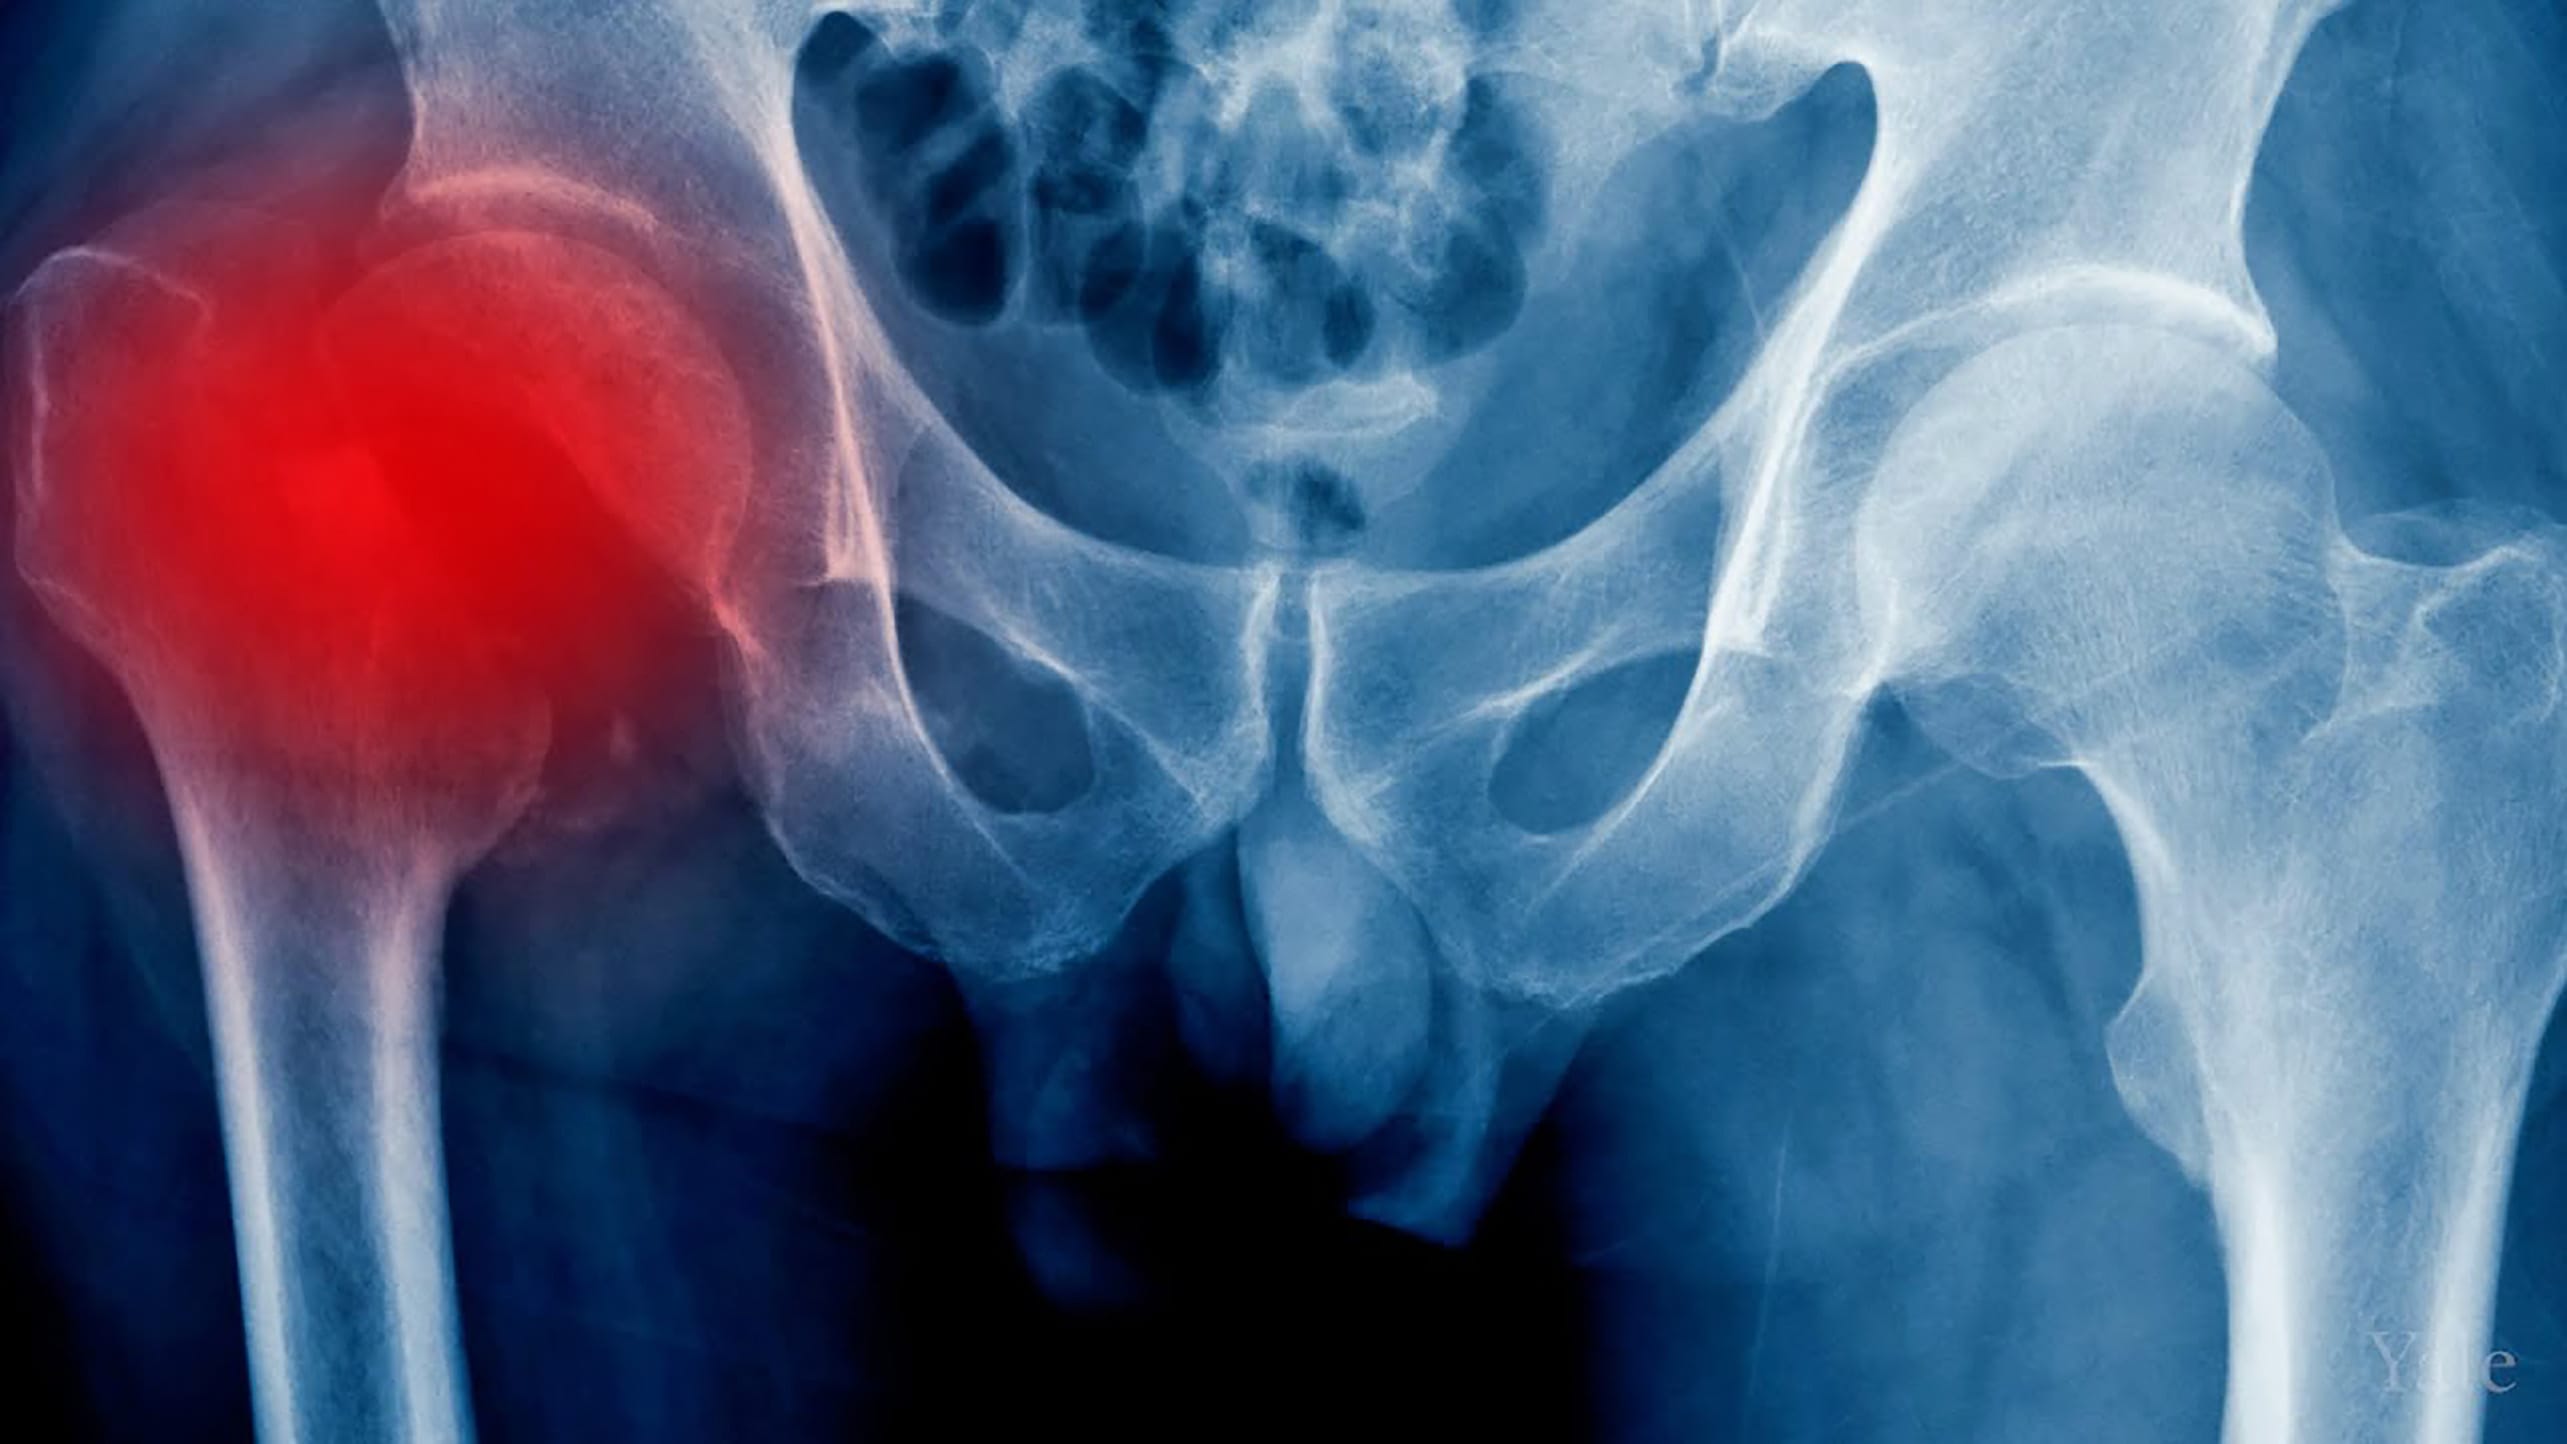

From www.yalemedicine.org

Geriatric Hip Fractures > Fact Sheets > Yale Medicine Osteoarthritis Hip Fracture osteoarthritis of the hip causes pain and stiffness. the differential diagnosis of hip osteoarthritis includes the following: osteoarthritis of the hip results in pain, stiffness, and joint deformity. Use of assistive device for ambulation when needed; Physiotherapy interventions for the treatment of hip fracture should include: It can make it hard to do everyday activities like bending. Osteoarthritis Hip Fracture.